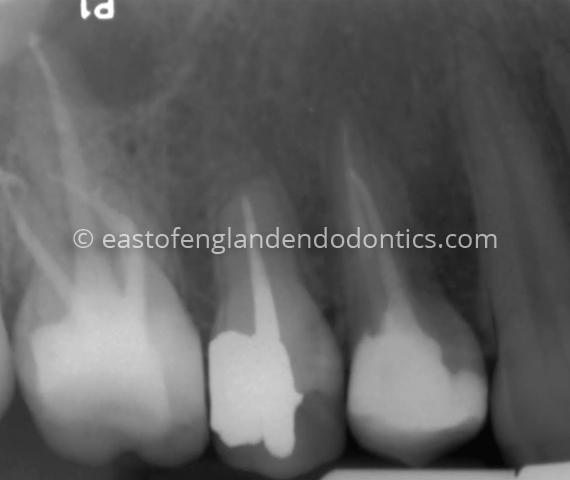

Case StudiesPost-operative radiograph LL6